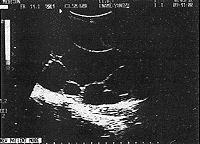

患者女,42岁。腹部包块4年伴胀痛一月余来诊。妇检:腹部膨隆如孕5+月大小,压痛明显,边界清,表面光滑,活动度差,叩之呈浊音,因肿块较大无法触及子宫附件。B超检查:于中下腹可探及约126mm×96mm的无回声区。壁规整,内被多个强光带分隔成大小不等的暗区(图1)。子宫附件显示不清,B超提示:盆腔巨大囊性占位:卵巢囊肿(粘液性囊腺瘤?)。剖腹探查术中见子宫如孕5+月大小质稍软,表面光滑,透亮,活动度差。左侧附件与子宫粘连。切除次全子宫及左侧附件。病检结果:子宫包囊虫病。

图1 子宫包囊虫病